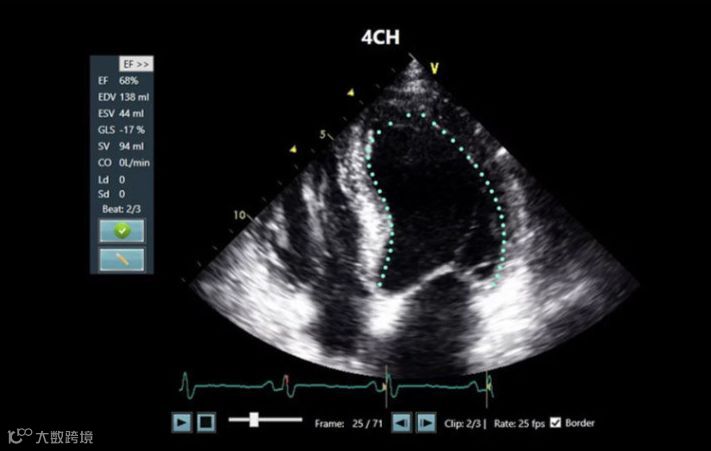

六、DiA Imaging Analysis:Lvivo心脏超声AI软件

DiA Imaging Analysis推出了心脏超声AI软件,它能自动分析心脏超声图像。LVivo可快速、准确地进行心内膜追踪,从而实现自动对左心室功室整体和分段的测量。DiA Imaging Analysis还和GE医疗合作推出了Lvivo EF App。Lvivo EF App可集成到Vscan口袋超声中,结合口袋超声与LVivo EF的优势,可帮助医生辅助诊断疑似心力衰竭或心源性休克的患者的心脏功能。